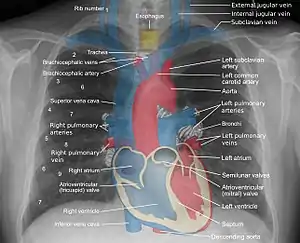

Mediastinum anatomy.

Some mediastinal structures on a chest radiograph.